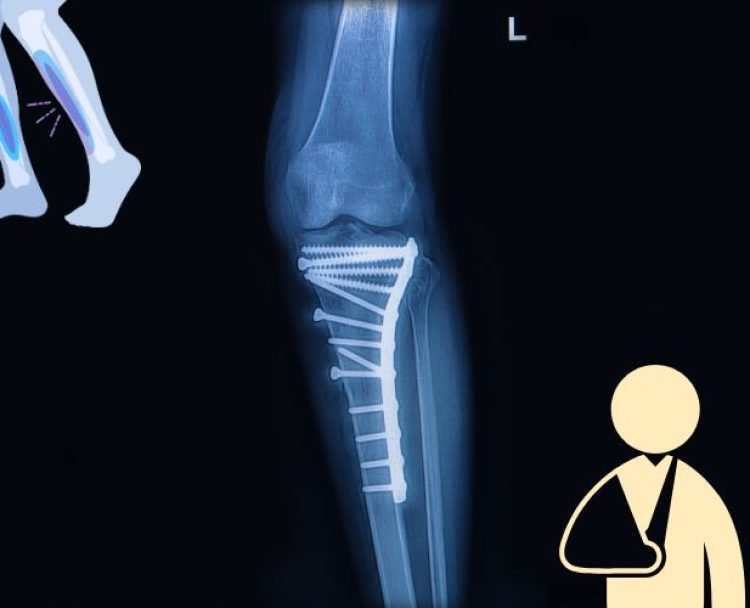

Trauma Surgery

Trauma injuries require immediate and expert care. Dr. Bajaj's extensive experience in trauma surgery guarantees the best outcomes for your recovery journey.